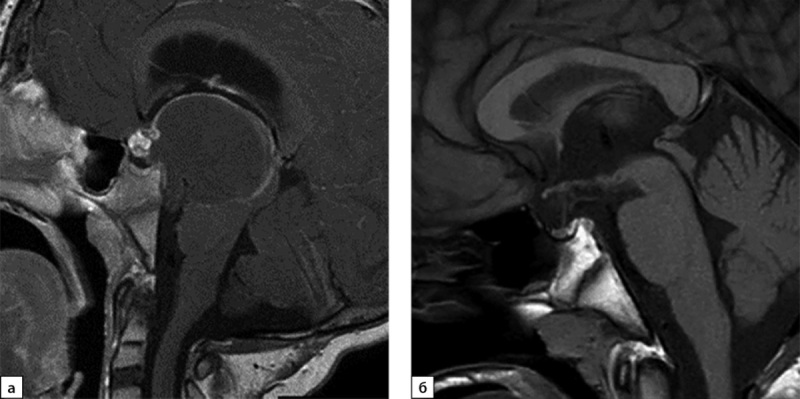

This article describes the first experience of successful use of growth hormone (GH) in combination with an aromatase inhibitor (AI), in a 14-year-old boy. At the age of 7, he presented with headaches, nausea and vomiting, and MRI revealed a craniopharyngioma (CP). An Ommaya system was implanted, and radiation therapy was performed. As a result of treatment, GH deficiency and secondary hypothyroidism developed. At age 9 years, signs of puberty appeared. Growth rate remained satisfactory until the age of 14 years. At the age of 14 growth rate slowed down, which was the reason for appointment. Upon examination, the bone age was 16 years and the projected final height without therapy was 162 cm. Given the poor growth prognosis, IA anastrozole in combination with GH was prescribed. During two years of therapy the growth gain amounted to 12.5 cm. This observation demonstrates that normal growth rates in patients with CP do not indicate preserved somatotropic function of the pituitary gland. With preserved sexual function, early or premature puberty may be observed. In such cases, IA can be prescribed in addition to GH - these are medications that inhibit the closure of growth. GH therapy in combination with IA is highly effective and safe in patients with GH deficiency after treatment of KF during puberty and allows to achieve good growth parameters.